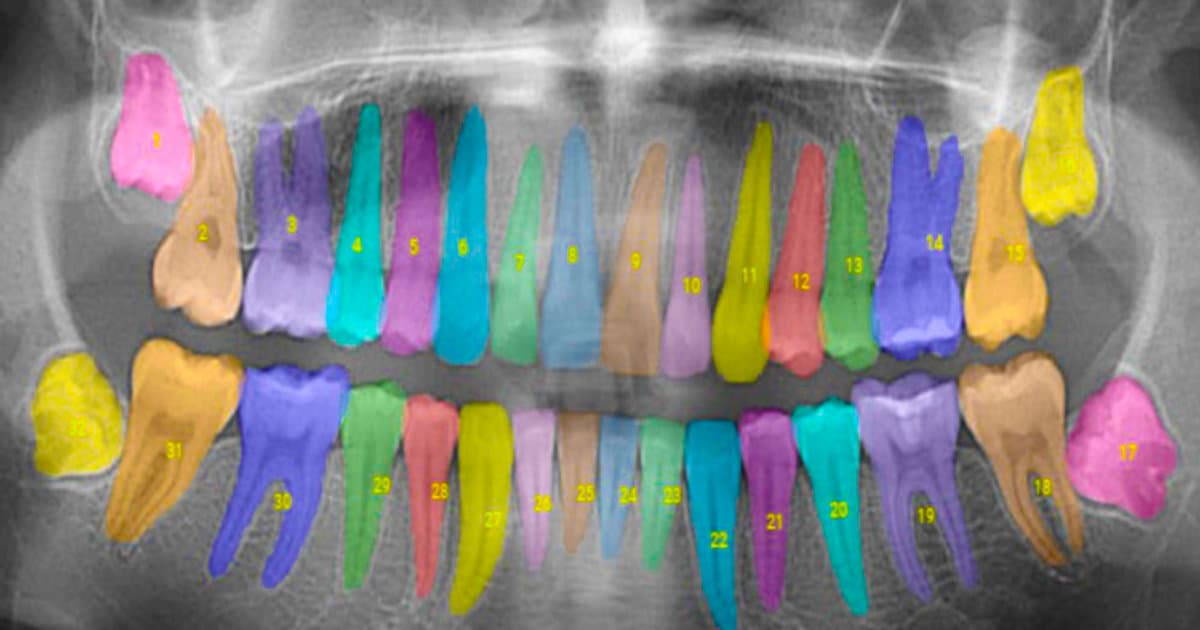

Cone Beam 3D Imaging is another powerful tool in the arsenal of digital dentistry. It allows dentists to view clear, detailed, 3D images of the patient's teeth, soft tissues, nerve pathways, and bone in a single scan. This imaging technology is particularly beneficial in complex cases, like implant planning, evaluating the jaws and face, diagnosing temporomandibular joint disorder (TMJ), and much more.